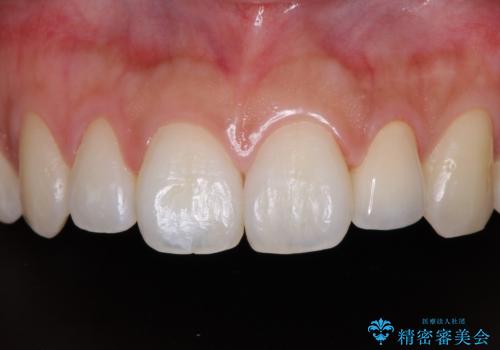

保険診療の黄ばんできた前歯をオールセラミッククラウンで自然な歯に

前歯の色が気になる【オールセラミッククラウン】